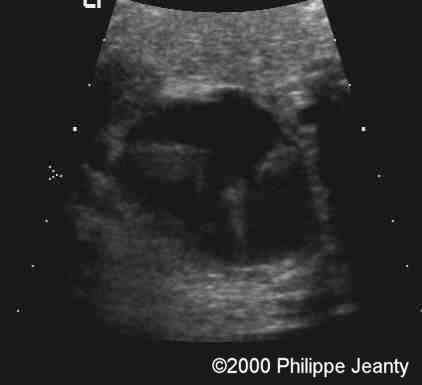

One hand demonstrated a clear simian crease

case0020-4

The other had both a simian crease and an unusual overlapping of the fingers viewed in this image and in the next (clinodactyly of the 5th finger)

case0020-4b

Other view of that same hand: note the clinodactyly.

case0020-5